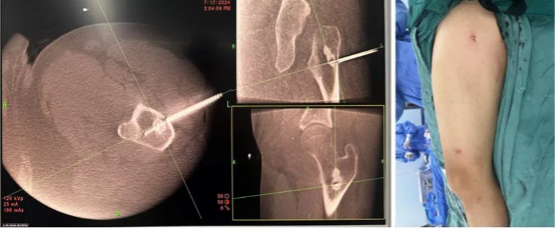

图3:术中影像及手术穿刺口

入院后诊断为中心型股骨髓腔骨样骨瘤,本型临床症状不如皮质型明显,部分患者疼痛隐匿,单纯射频消融效果较好。入院后第二天全身麻醉后导航下行左侧股骨病灶射频消融术,选择消融针尺寸为15毫米,消融时间11分30秒。术后第二天患者自诉原有疼痛不适症状缓解90%。术后复查MRI可见骨内明显的椭圆形消融范围,精准对应了23*19毫米的消融范围。